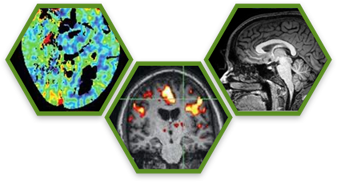

Nuclear Medicine

Molecular Imaging

Magnetic Resonance Imaging

Multimodality